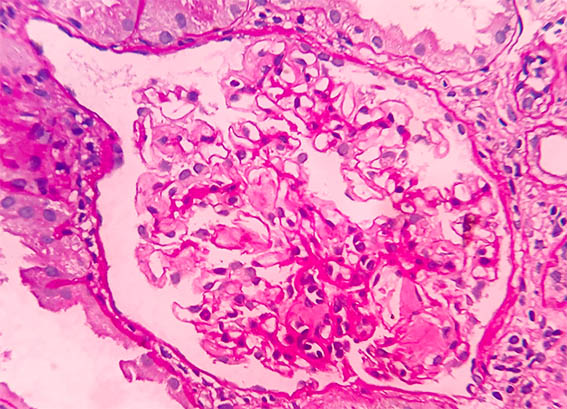

Un paciente de 53 años con diagnóstico de infección por VIH 2 años antes, en tratamiento anti-retroviral, es evaluado por 2 semanas de edemas, sin otros síntomas. En las pruebas de laboratorio el hemoleucograma es normal. Conteo de CD4: 510 /mm2; carga viral: menos de 500 copias /mL. Se documenta síndrome nefrótico, con proteinuria de 7,5 g/24h, hipoalbuminemia y dislipidemia. Creatinina sérica: 1,0 mg/dl, BUN: 14,0 mg/dL. Estudios para virus de hepatitis: negativos. ANAs y anti-DNA negativos; complemento sérico normal; VDRL no reactivo. Electroforesis de proteínas en suero: normal.

Se hace biopsia renal, observe las imágenes.

Figura 1. H&E, X200.